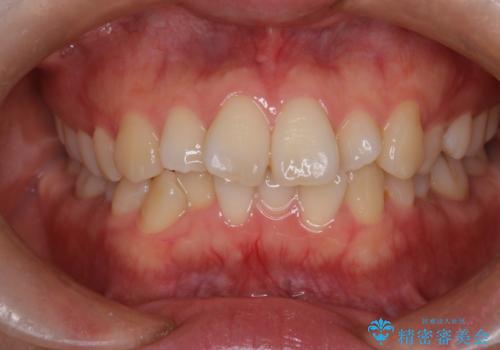

目立たない矯正で八重歯を改善

- 左上の八重歯を気にされて来院されました。精密な検査の結果、歯列全体を広げながら八重歯を奥へ移動させることで、美しい歯並びと機能的な咬み合わせが得られると診断。患者様のご希望に合わせ、透明で目立ちにくい**インビザライン(マウスピース矯正)**による治療計画を立案しました。抜歯を避け、歯を少しずつ遠心(奥)へ移動させることで、歯が並ぶスペースを確保し、叢生(歯のデコボコ)を改善します。

今回の矯正治療では、透明なマウスピース型の装置インビザラインを使用しました。この装置は目立ちにくく、取り外しが可能なため、食事や歯磨きも普段通りに行えます。遠心移動という方法で奥歯を後方に動かし、前歯を並べるためのスペースを確保。これにより、抜歯することなく、左上の八重歯を含む叢生を効果的に改善し、整った美しい歯並びと良好な咬み合わせを獲得していただけました。